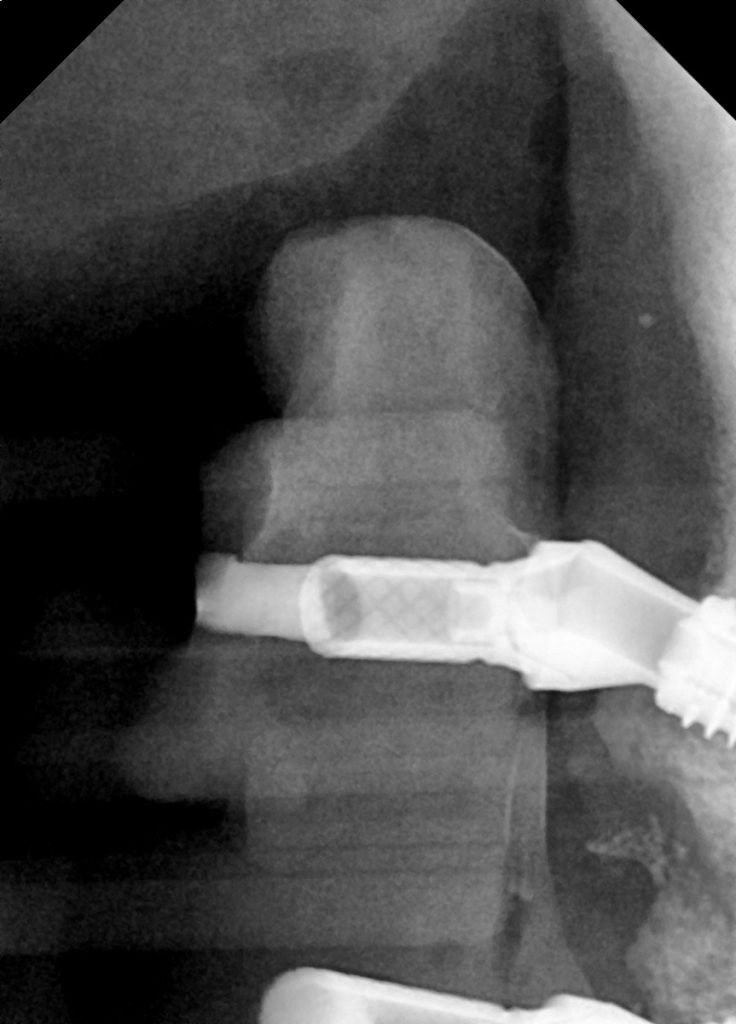

SK: The patient was fully aware from the start that with this type of bridge, his teeth weren’t going to feel like individual teeth and that there would be a thin substructure (bar) connecting the teeth.

The occlusion was carefully managed to ensure loading was spread out along the whole bridge rather than it being heavy in certain areas. This allowed a more even distribution of loading across all implants.

We also explained the concept of a shortened dental arch as we couldn’t place the implants too distal in the 6/7 areas due to insufficient bone. The patient was fully aware that the full arch bridge was going to be 6-6 in the final prosthesis and 5-5 in the temporary prosthesis in order to reduce any cantilever force and reduce fractures.